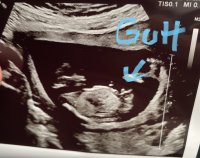

Da har vi vært på ul,og alt ser strålende ut!:D Jeg er så letta!:smug:

Å så ser det (ganske tydelig) ut som det blir en lillebror:joyful:

Kroppen målte til 13+2,akkurat det jeg har går ut fra. Men hodet målte til 13+3,og sønnen jeg har fra før har alltid hatt et stort hode,så det hørtes riktig ut:hilarious::hilarious: